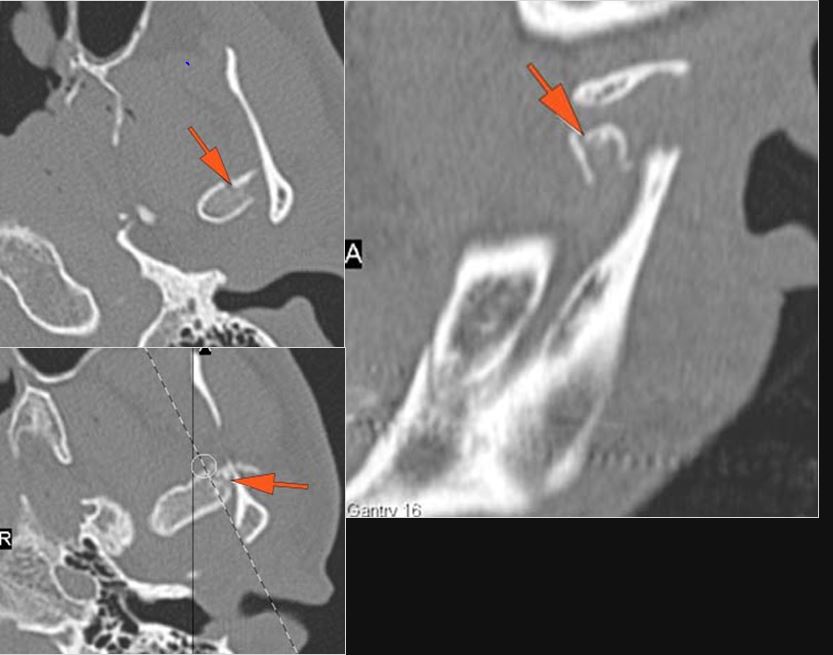

The condylar head and fossa as well as the temporomandibular joint space are abnormal. [Yes/No]

There is condylar fracture either within or outside of the joint capsule, or with or without involvement of the articular surface of the condylar head. [Yes/No]

There is evidence of radiodense intra-articular osteochondral fragments. [Yes/No]

There is bony injury or displacement of the external auditory canal and/or other evidence of temporal bone injury. [Yes/No]